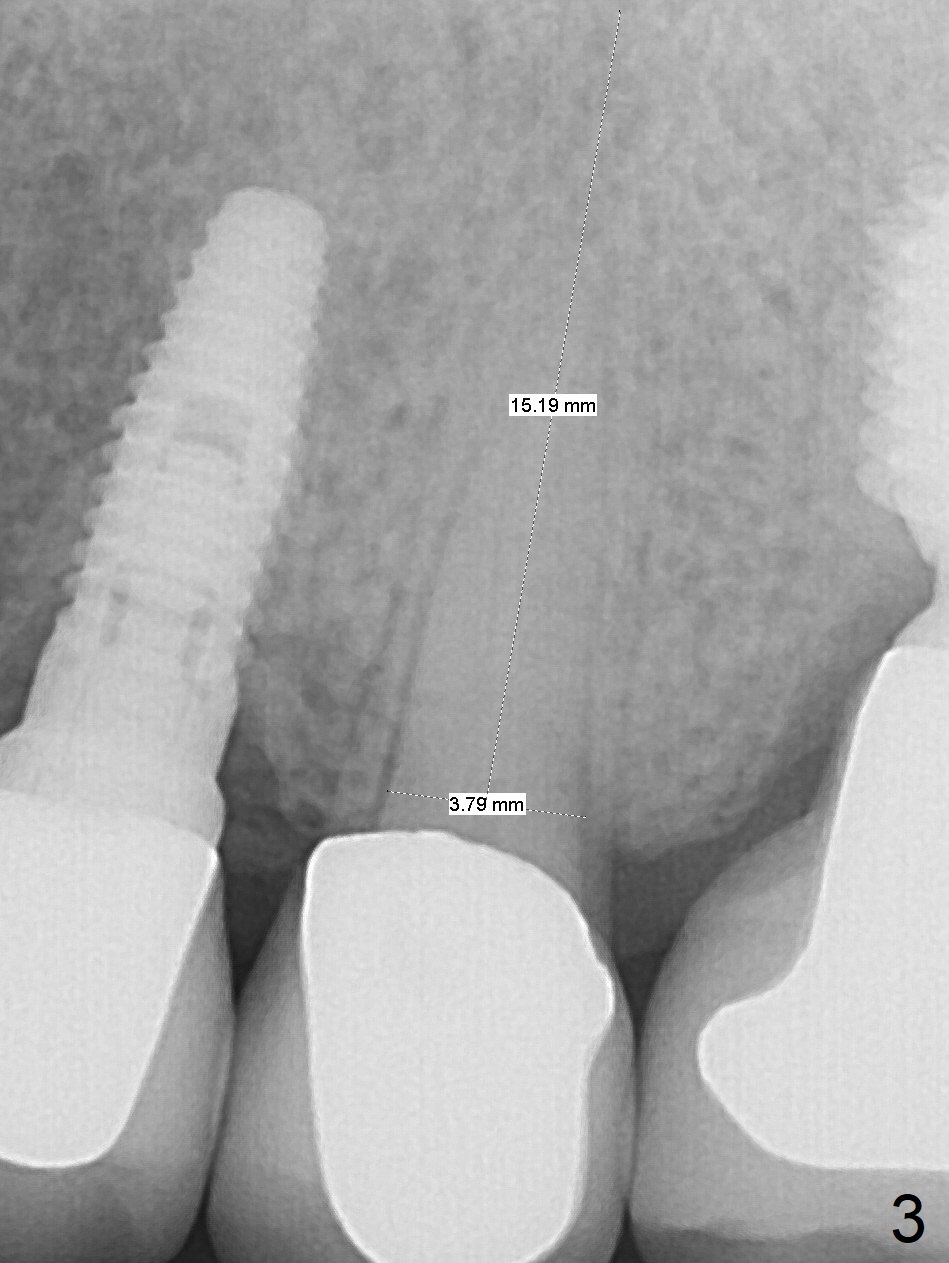

Failure

A 75-year-old man has bite pain at #13 after RCT (root resorption, Fig.1). The tooth appears to be non-salvageable (Fig.2). There seems to be sufficient bone for the longest tissue-level implant (Fig.3,4). Take preop PA and intraop one as soon as a 2 mm drill is used for trajectory confirmation.